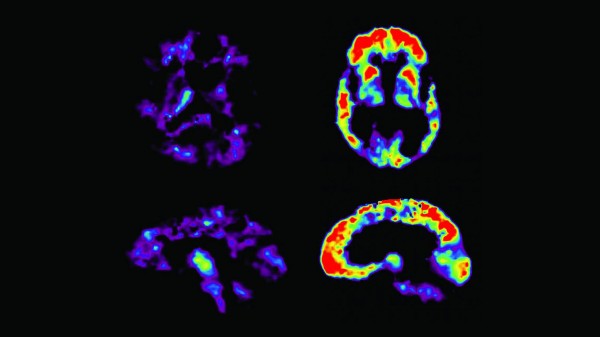

Avete letto le storie di nuovi test per l'Alzheimer, che si suppone siano proprio dietro l'angolo? Gli annunci: un test semplice del sangue, un test dell'occhio, anche un test dell'odore, potrebbero dimostrare se hai un rischio elevato di Alzheimer...